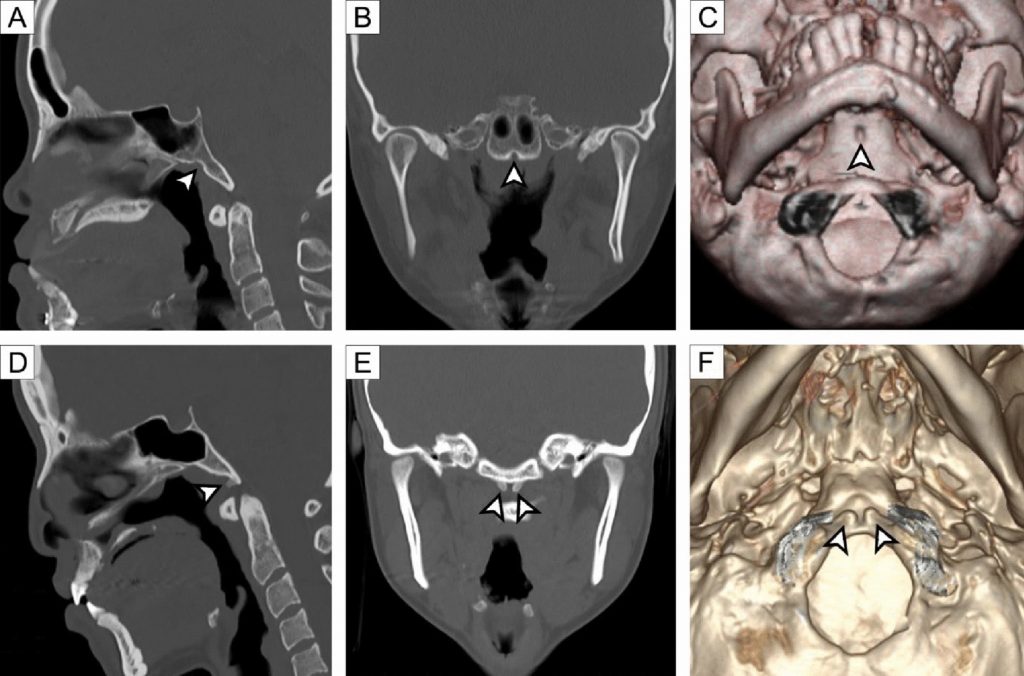

The clivus is an important landmark in neurosurgery and radiology due to its proximity to critical neurovascular structures. Anatomical variations of the clivus are diverse and may mimic pathological lesions on imaging. However, data on their prevalence in Southeast Asian populations are limited. This study investigated the prevalence and morphology of clival anatomical variations in the Thai population using computed tomography (CT). A total of 429 cranial CT scans (233 males and 196 females; mean age 39.5 ± 15.4 years) from patients without cranial abnormalities were retrospectively analyzed. The CT images were examined for fossa navicularis magna (FNM), basilar processes (BP), canalis basilaris medianus (CBM), tubercle at the anterior margin of the foramen magnum (TFM), condylus tertius (CT), and arcus praebasiooccipitalis (AP). FNM was the most common variation, identified in 107 cases (24.9%), followed by CBM (9.6%), BP (7.2%), and TFM (4.9%). CT (1.6%) and AP (0.5%) were rare. The CBM appeared as superior recess (5.1%), channel (2.6%), and inferior recess (2.3%) types. No significant sex differences were found for any variant (p > 0.05). These findings indicate that clival variations are relatively common in the Thai population, with FNM being the most prevalent. Knowledge of these variations is essential for accurate radiological interpretation and for planning neurosurgical procedures involving the skull base. Population-specific data such as these are crucial to improve diagnostic accuracy and surgical safety among Thai individuals.